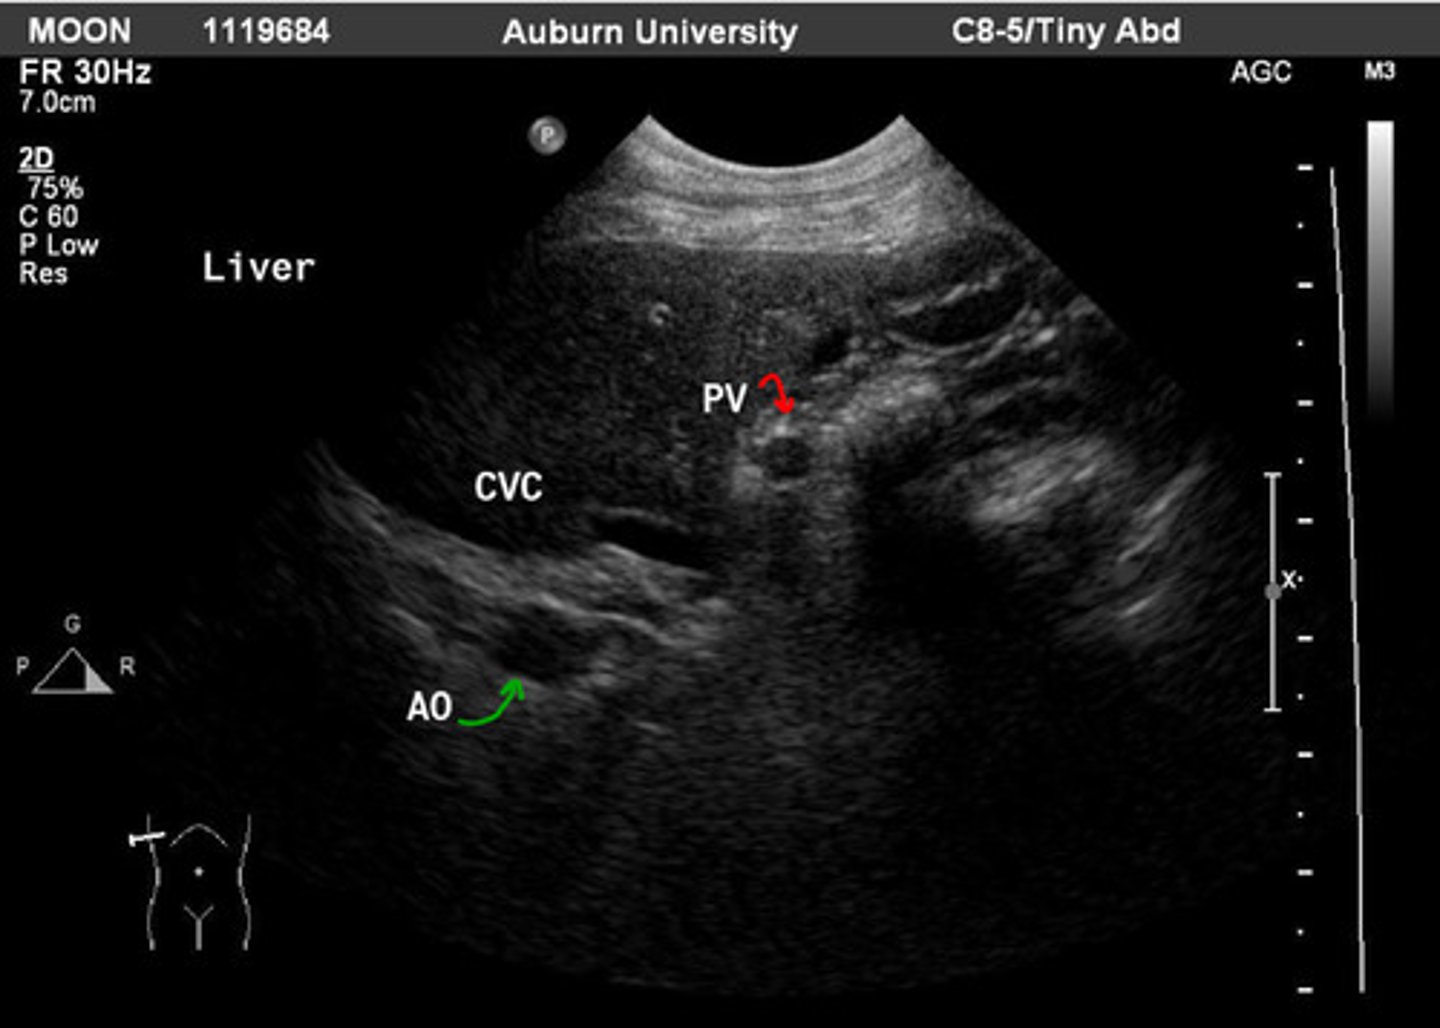

right intercostal window

which window can you see the hepatic hilus?

red- portal vein

green- aorta

ID green and red

red- portal vein

green- aorta

ID red and green

aorta

which is more dorsal: aorta or portal vein?